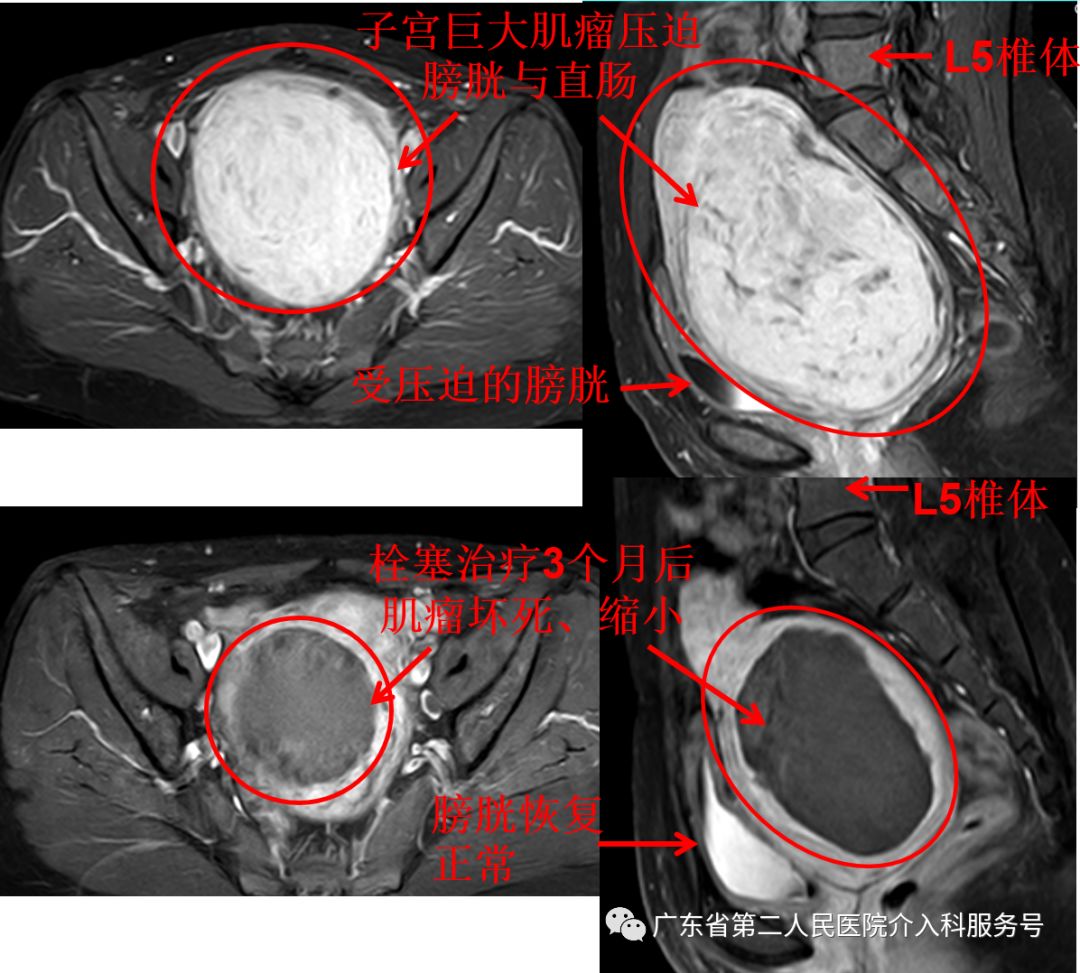

治疗后差不多1个月,王女士的“大姨妈”驾到,量正常,第6天即干净,再也没有淋沥不净的尴尬。3个月后,王女士例假依然正常,已没有贫血貌,现在久坐后站立时再也没有出现眼前发黑(黑蒙)的现象,腹部平坦,大小便正常。王女士高兴的说:终于摆脱“大姨妈”来时排山倒海,淋沥不净的烦恼,关键是可以和其他女性一样保留子宫,正常来月经,没有血块,不会淋沥不净,生活也舒坦了。门诊复查血红蛋白在正常范围,磁共振如下(子宫肌瘤已坏死、吸收、缩小(8cm*7cm*5cm),随后还是的肌瘤还会继续吸收、缩小)。